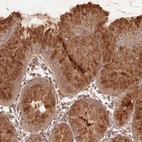

Immunohistochemical staining of human stomach shows strong cytoplasmic and membranous positivity in glandular cells.